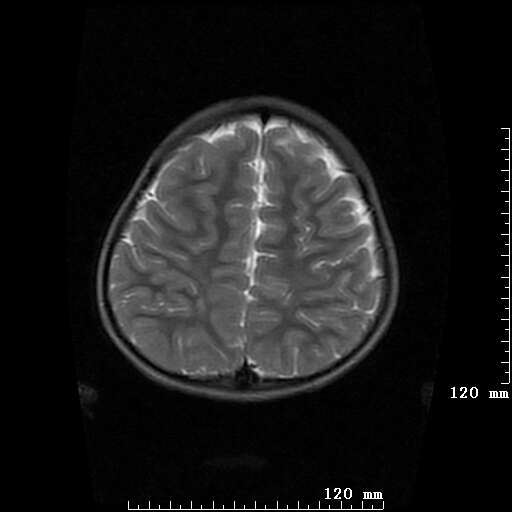

女,7岁,三岁才说话、走路。现智力尚可,走路不稳。临床怀疑大脑发育不全。

考虑 脑白质发育不良

脑折质变薄,双侧侧脑室稍扩张,支持考虑脑折质发育不良

侧脑室周围白质软化症。

考虑胼胝体发育不全,髓鞘形成不良。

支持考虑胼胝体发育不全,髓鞘形成不良。

脑裂畸形伴灰质异位

侧脑室周围白质数量减少,侧脑室不对称性扩大,左侧侧脑室后角呈方形改变,脑沟加深,结合临床考虑脑室周围白质软化症(pvl)。期待结果!

只看出灰质异位

支持脑白质发育不良。